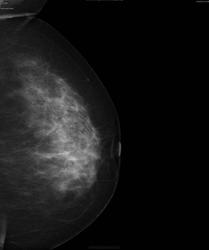

В правой железе. Кранио-каудальные проекции.

Кранио-каудальные - понятно. На мой взгляд - спорно насчет июньской: чего бы это узлу быть в другом месте при всех остальных сохраненных соотношениях. Я-то пытаюсь протолкнуть идею, что узел был и в июне, и что он виден на косых (пост фактум).

Вадим, а показать, где на первом рак в косых проекциях?

Мне кажется, что в июне не было. Покажите. Посмотрим вместе.На рабочей станции качество рентгенограмм выше чем JPEG.

Предлогаю еще случай. Женщина 49лет. Снимки за июнь 2012г.